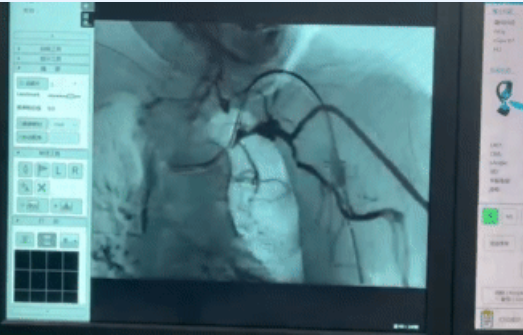

内瘘血管局部消毒、18G套管针穿刺、连接高压注射泵、DSA投影定位、C型臂试旋转,随着一连串有条不紊的指令发出,3D-DSA即将实施,在场医护屏气凝神。“开始成像”,介入治疗中心曹志国技师发出指令并按下按钮。只见高压泵以3毫升/秒速度快速推注造影剂,同时C型臂延既定中轴线旋转一周,6秒钟,造影结束,与此同时操控台的显示器呈现出3D-DSA影像。“漂亮!”在场医护异口同声发出赞叹。

此时,张东亮主任紧盯屏幕反复观看血管影像,3分钟后最终结论下达:“可以拔除颈内静脉导管,不需要介入治疗。”结束3D-DSA操作,随后拔除了留置的颈内静脉导管,医护人员送老人回病房观察。

果然,赵奶奶不需要采取介入治疗,拔除导管后,“肿胀手综合症”也随之消失,这时大家再次回顾3D-DSA影像,集体进行了病例讨论、总结了经验。赵奶奶欣喜地用上自体动静脉内瘘开始了新的透析治疗,导管拔除后的伤口愈合良好,再也不担心脖子上有根管子了,终于可以正常洗澡、睡觉、活动上肢。

3D-DSA技术首次应用在透析患者血管通路后,又有几例透析患者成功应用,为临床解决了实际难题,且造影剂使用剂量大幅减少至传统CT成像的1/4,时间缩短一半。